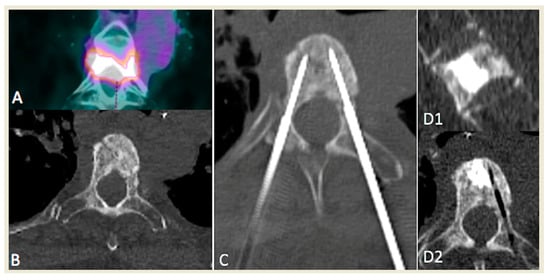

2.2. RFA Technique